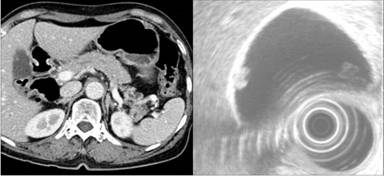

A seventy-two-year-old female patient visited our Department of Surgery due to incidental discovery of a cystic lesion in the distal pancreas and a gallbladder polyp during routine medical check-up. She did not complain any specific symptom and have significant medical history. The image study showed a cystic mass of approximately 2 cm in size in the tail of the pancreas and a gallbladder polyp of about 1 cm (Figure 1). Routine chemistry and tumor marker levels (CA 19-9, CEA) were all within normal limits. The patient was scheduled for spleen-preserving laparoscopic distal pancreatectomy with concomitant laparoscopic cholecystectomy for an intraductal papillary mucinous neoplasm of the pancreas and gallbladder polyp.

Figure 1. Preoperative image study. Abdominal CT scan showed a cystic mass in the tail of the pancreas and US revealed a gallbladder polyp of about 1 cm in size. |